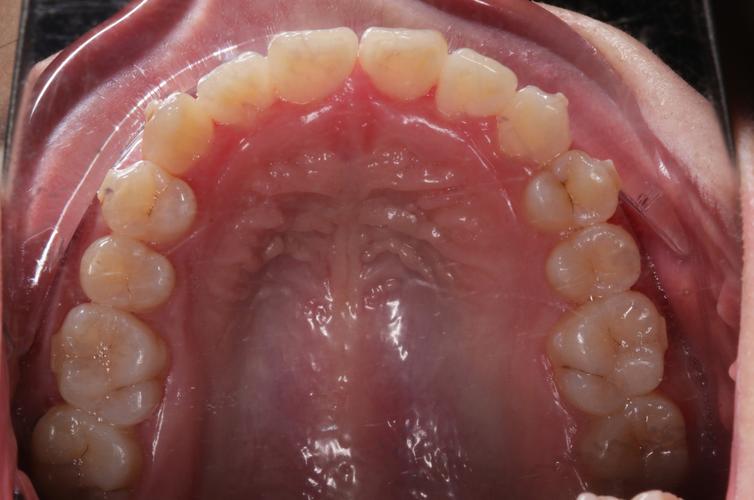

上牙列咬合面观:

(图片来源网络,侵删)- 目的: 观察上颌牙齿的排列情况(拥挤、间隙、扭转)、牙冠形态、龋坏、磨损、修复体、咬合关系(后牙尖窝接触)、牙弓形态、腭盖形态。

- 拍摄要求: 患者张口,上颌平面与地面平行,镜头垂直于牙列咬合面,用反光板或口镜牵拉颊部和舌体,充分暴露整个上牙列咬合面。